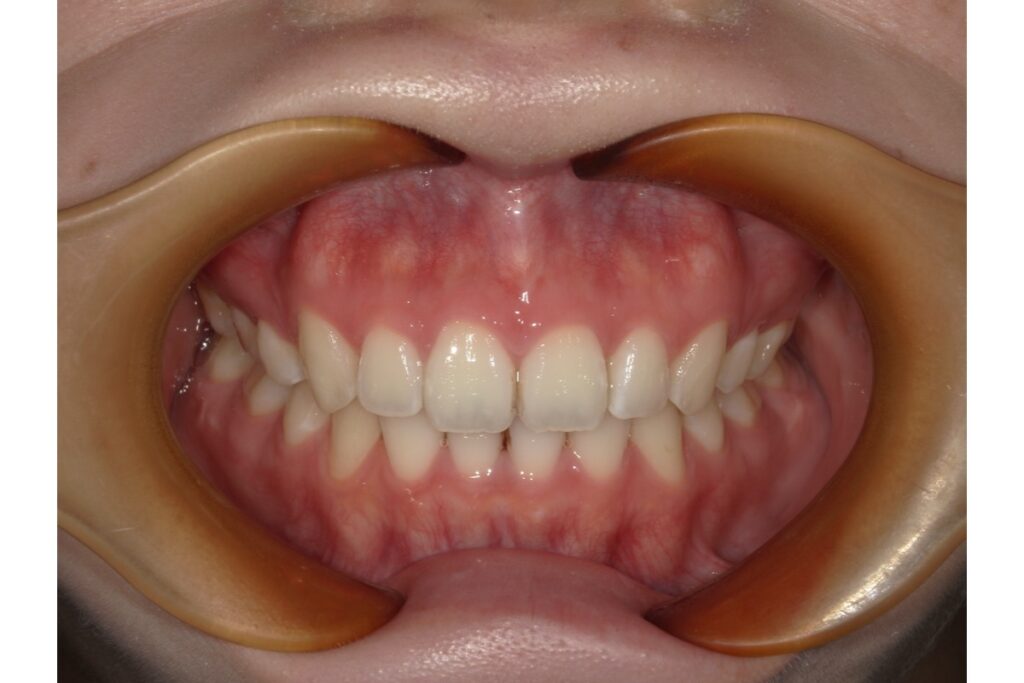

治療後

治療前後の写真を見比べると、前歯の引っ込み具合がよく分かります。

歯を抜いて治療を行っているので、横から見たときの変化がとても分かりやすいかと思います。歯だけではなく、横顔も口元がスッキリしますよ。

インビザライン治療は軽度な叢生などを治す治療方法だと思われがちですが、実際は抜歯症例も扱うことができます。